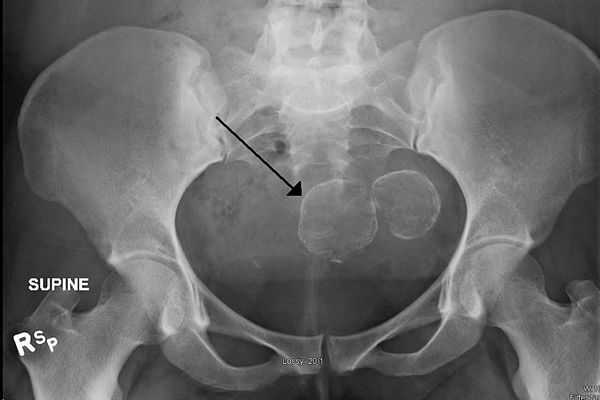

• В 3-10% всех миом выявляют очаги обызвествления